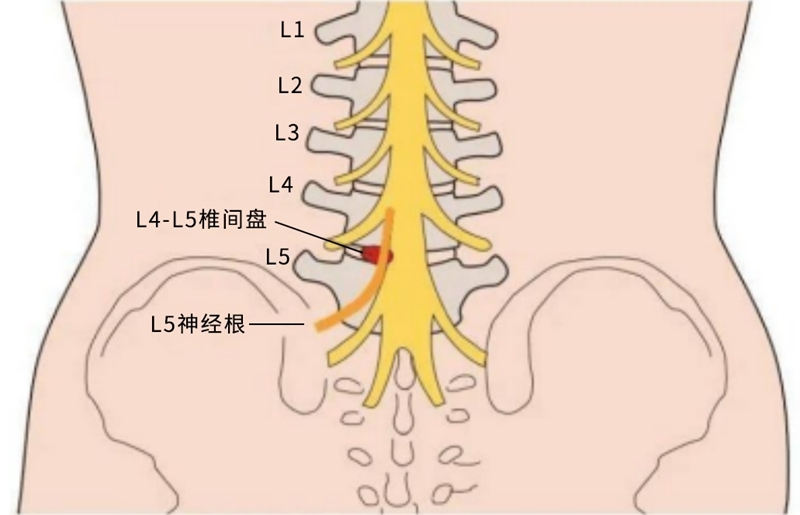

L5神经根解剖

L5神经根是腰椎间盘突出常常累及的神经根。尤其是腰4/5节段的椎间盘突出。临床可从肌力检查、感觉检查及反射检查三个方面来判断L5神经根定位的主要标志性表现。

L5神经根瘫是指L4-5之间的椎间盘突出,压迫了L5的神经根,引起临床的症状。

1.术前病理因素致L5神经根(行走根或出口根)受压;

2.术中L4/5损伤L5行走根或者L5骶1节段损伤L5出口根。

1. 解剖学上L5神经根移行区域长;致压因素复杂;

2. L4/5和L5S1两个节段发病率高;

3. 侧隐窝及出口区易骨性狭窄;